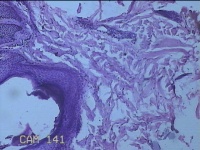

右侧头部息肉结节

性别

男

年龄

39岁

临床诊断

头皮良性肿瘤

一般病史

发现右侧头部息肉结节20余年。

标本名称

右侧头部息肉组织

大体所见

灰白暗红色组织1.2x1x0.8cm一块,表面带梭形皮肤1.2x0.8cm,皮下见结节1.2x0.9x0.3cm一个,切开结节呈实性,切面灰白暗红色,质软。